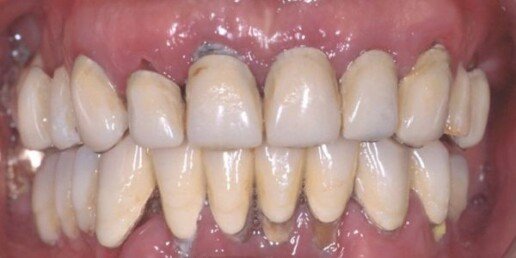

Caso 3

In questo caso si è reso necessario il rialzo del seno mascellare bilaterale, per la ricostruzione dei tessuti duri (osso) e dei tessuti molli (gengiva). La paziente ha portato 25 anni una protesi incongrua, questo le ha provocato la perdita di tanto osso. Con la tecnologia CAD-CAM, è possibile ricostruire le protesi, partendo da un disegno al computer, e poi produrla attraverso una macchina che costruisce in 3D il pezzo in zirconio o altro materiale. Il tecnico di laboratorio provvede poi a personalizzare con la porcellana estetica.

Prima

Dopo